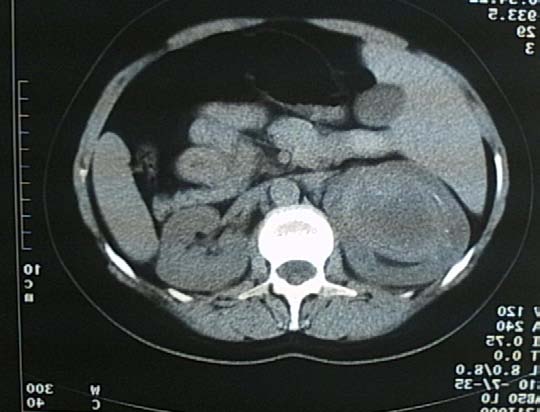

L'examen à la lampe fente montrait au niveau de l'oeil droit un Tyndall cellulaire de chambre antérieure une croix, une rétine appliquée sous gaz à 50%. Une uvéite granulomateuse modérée bilatérale. Le fond d'oeil gauche montrait une papille hyperhémiée, des décollements séreux de rétine, multiples polylobés (figure A), confirmés par la tomographie en cohérence optique (OCT). L'OCT a également montré des décollements de l'épithélium pigmentaire (figures I, J).

L'aspect fluoangiographique a montré aux temps précoces, un remplissage irrégulier, retardé de la choroïde (figureB); puis de multiples points hyperfluorescents (pin-points) apparaissent, associés à une accumulation progressive du colorant dans l'espace sous-rétinien (figures C, D) Les taches blanc jaunâtre, profondes sont hypofluorescentes aux temps initiaux, puis s'imprègnent progressivement à la phase tardive. Une hyperfluorescence papillaire tardive est fréquente (figure E).

L'angiographie au vert d'indocyanine retrouve une hypoperfusion choroïdienne, tâches hypofluorescentes, arrondies, de petite taille, à distribution homogène, visibles aux temps inter-médiaires, persistant ou disparaissant aux temps tardifs (figures F, G,H).